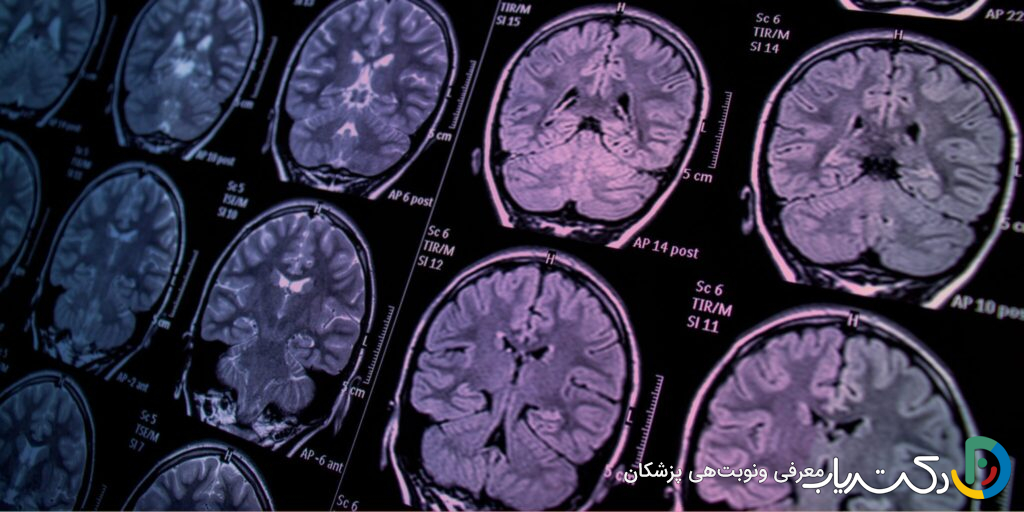

• تشخیص قطعی با تصویربرداری: تنها راه مطمئن برای تشخیص یا رد وجود تومور مغزی، استفاده از روش‌های تصویربرداری پیشرفته مانند MRI است.

تصویربرداری مغز: استاندارد طلایی تشخیص

اگر نتایج تاریخچه پزشکی و معاینه عصبی مشکوک باشد، گام بعدی تصویربرداری از مغز است. این تنها راه برای تأیید یا رد قطعی وجود تومور و مشاهده مستقیم ساختار مغز است.

• MRI (تصویربرداری رزونانس مغناطیسی): این روش بهترین، دقیق‌ترین و حساس‌ترین ابزار برای مشاهده بافت نرم مغز و تشخیص تومورهاست. اغلب با تزریق یک ماده حاجب (کنتراست) انجام می‌شود. این ماده از طریق ورید تزریق شده و در نواحی‌ای که سد خونی-مغزی (یک سد محافظ طبیعی) آسیب دیده است، مانند اطراف تومورها، تجمع می‌یابد و باعث می‌شود تومور در تصاویر MRI به صورت یک ناحیه درخشان و بسیار واضح دیده شود.

• CT Scan (توموگرافی کامپیوتری): این روش سریع‌تر از MRI است و در شرایط اورژانسی یا در بیمارستان‌هایی که MRI در دسترس نیست، بیشتر استفاده می‌شود. اگرچه به اندازه MRI برای بافت نرم دقیق نیست، اما می‌تواند وجود توده‌های بزرگ، خونریزی، تورم شدید یا هیدروسفالی را به‌خوبی نشان دهد.